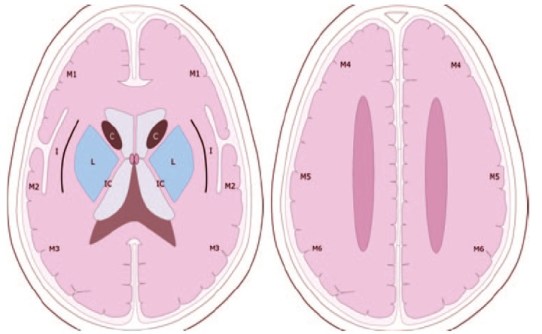

El Alberta Stroke Programme Early CT Score (ASPECTS) es un sistema estandarizado de interpretación de la TAC cerebral para los ictus isquémicos de la circulación anterior. Interpretación:

- El análisis se realiza sobre dos cortes axiales de la TAC

- El primero a nivel del tálamo y ganglios de la base (plano A).

- El segundo adyacente al borde superior de los ganglios de la base, sin que se visualicen los mismos.(plano B).

- En los dos planos, el territorio de la arteria cerebral media se divide en 10 regiones, valorando cada una en 1 punto.

- M1 : región cortical anterior de la ACM

- M2 : región cortical lateral al ribete insular.

- M3 : región cortical posterior de la ACM

- M4, M5, M6 : región cortical anterior, lateral y posterior de la ACM, aproximadamente 2 cm por encima de M1, M2, M3, respectivamente.( Plano B)

- M7 : Nucleo lenticular

- M8 : Núcleo caudado

- M9 : cápsula interna

- M10: ribete insular

- Se sustrae un punto por cada región donde se aprecia un cambios isquémico précoz (Hipoatenuación o efecto de masa local)

- Una puntuación del ASPECTS inferior o igual a 7 se asocia a una morbimortalidad elevada y mala recuperación funcional.

- Una puntuación ASPECTS de 10 significa que el TAC es normal.

- Una puntuación de 0 implica una afectación difusa de todo el territoio de la ACM

- El riesgo de hemorragia intracerebral siguiendo la terapia trombolíca es mayor si la puntuación es igual o menor de 7.